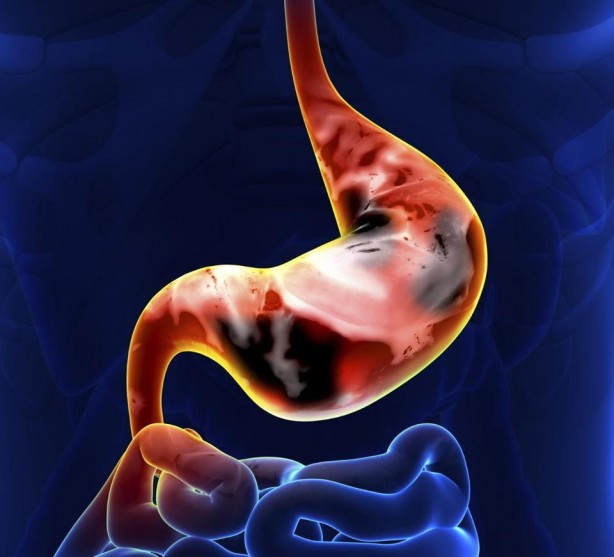

4. Kan kaybına bağlı olarak ortaya çıkan halsizlik, yorgunluk, kesiklik hissi, baş dönmesi, solukluk.

5. Siyah renkli dışkılama, kanlı kusma. Mide ve karın bölgesinde ele gelen sertlik.